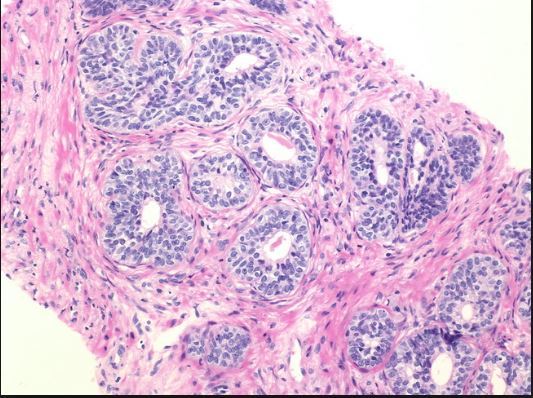

Q

Prostate:

adenosis or basal cell hyperplasia?

Adenosis

Here is BCH